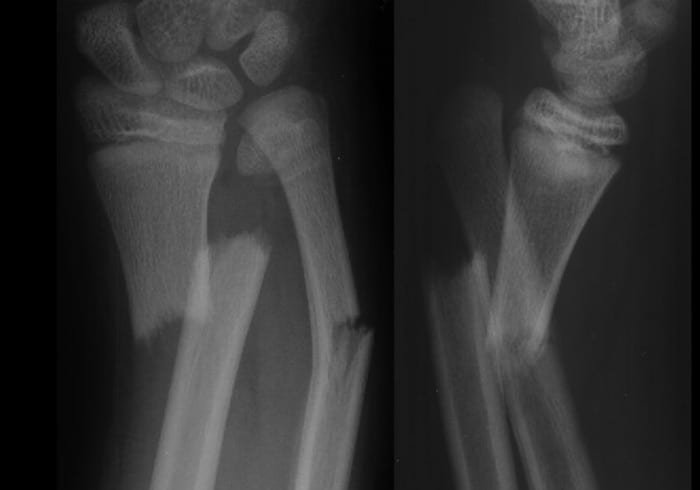

Compound or open fracture:

Fracture which communicates with external air is called compound or open fracture.

It is a definitive type of fracture which communicates with the external atmosphere due to break in the soft tissue cover.